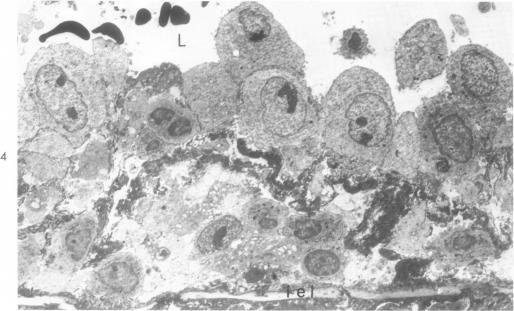

Thickening of arterial intima in rat cardiac allografts. A light and electron microscopic study.

Am J Pathol. 1971 Apr;63(1):69-84.